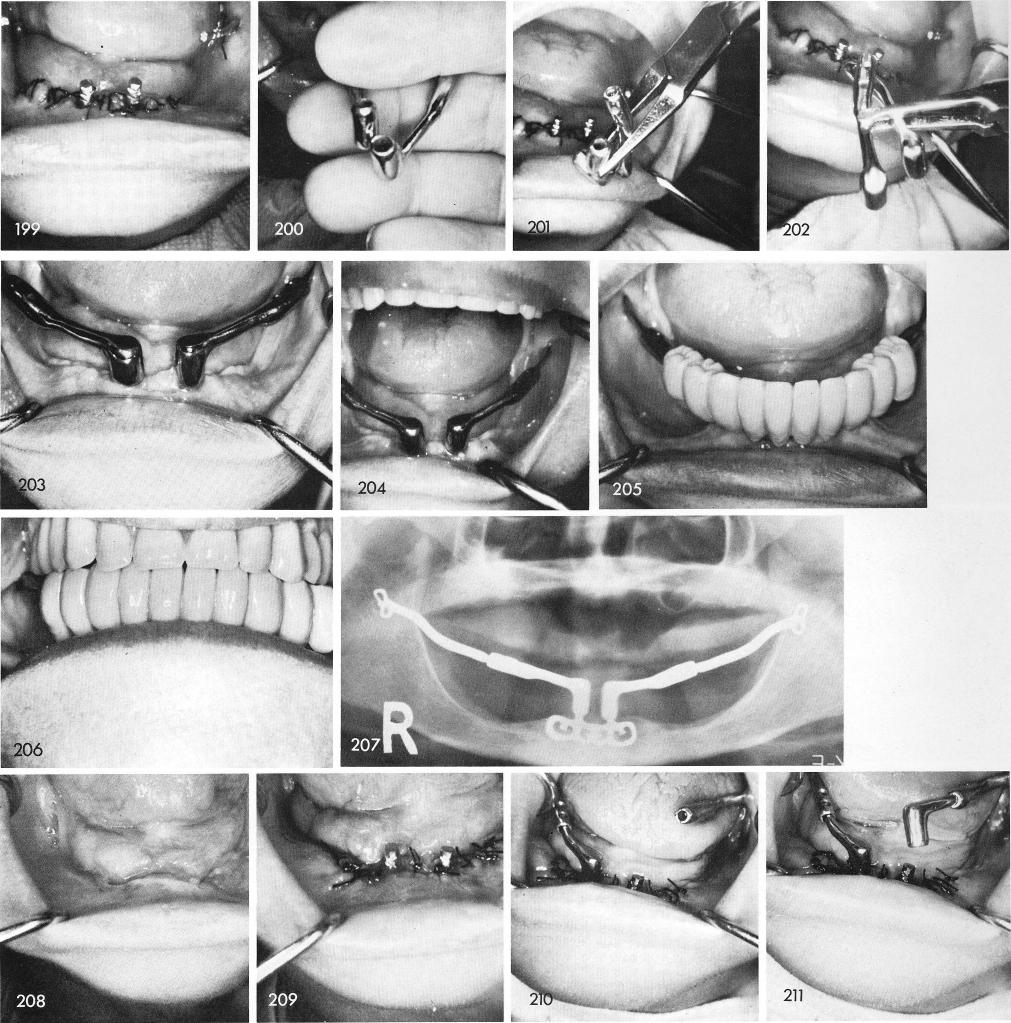

recast. Fig. 199 shows the tissues 24 hours later and the posterior horizontal extensions after the anterior portion was cut loose. The newly cast anterior copings with posterior horizontal tubes, figs. 200, 201, 202. The healed case, figs. 203, 204, and the teeth, figs. 205, 206, and post-operative x-ray, fig. 207.

Another case where a subperiosteal failed because of posterior tissue problems on both sides, fig. 208. The ramus blade is inserted and the tissues are sutured, fig. 209. The procedure continued to join anterior and posterior portions together, figs. 210, 211, 212. The healing was excellent, fig. 213, and the case completed, figs. 214, 215, 216, and the final x-ray, fig. 217.

1 Anterior coping & posterior horizontal tube of symphyseal ramus system